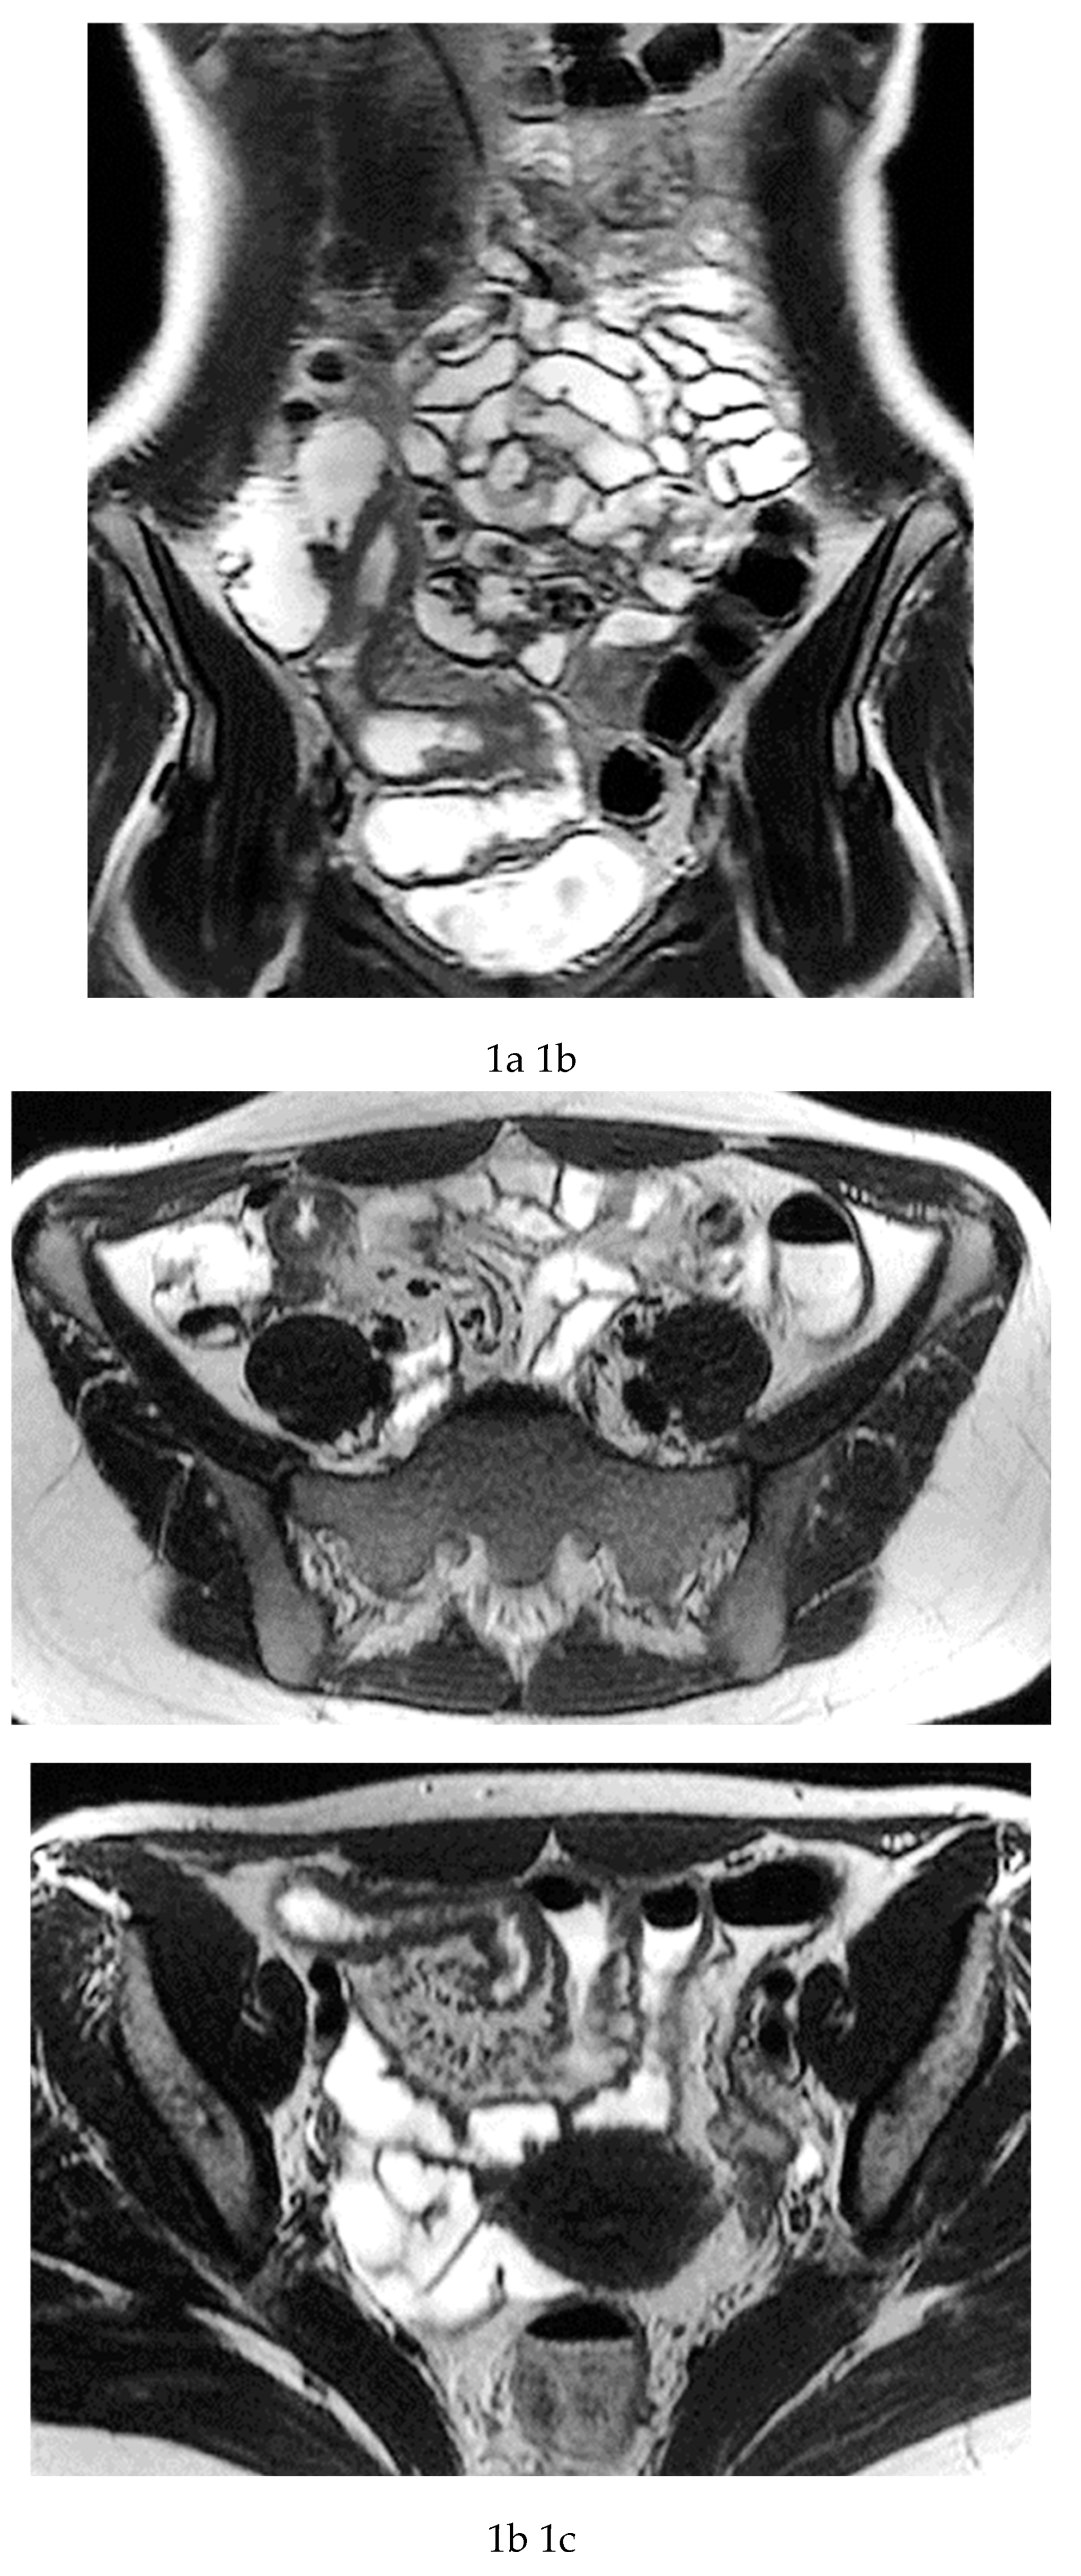

Multiparametric MRE protocols therefore combine a series of complementary sequences, each providing distinct and synergistic diagnostic information. T2-weighted sequences (

Figure 1a-c) are fundamental for a comprehensive morphological assessment of Crohn’s disease on both axial and coronal planes. They allow accurate definition of disease location, longitudinal extent, and severity, including evaluation of bowel wall thickening, luminal narrowing, and the presence of penetrating complications such as fistulas and abscesses at any level of the small and large bowel. These sequences are also essential for assessing extraintestinal manifestations of disease, including inflammatory changes of the surrounding mesenteric fat. Beyond structural assessment, T2-weighted imaging plays a pivotal role in the detection of inflammatory activity through the identification of mural and mesenteric oedema. Fat-suppressed T2-weighted sequences, in particular, enhance the conspicuity of high-signal oedematous tissue and currently represent the only imaging technique capable of directly demonstrating oedema at the level of the intestinal wall, mesenteric lymph nodes, and mesentery. Oedema is a hallmark of active inflammation and reflects increased vascular permeability and interstitial fluid accumulation [

Figure 1d-g), which reflect bowel wall vascularity and the degree of inflammatory activity. These sequences are essential for evaluating not only the affected bowel segments, but also associated inflammatory changes in the mesentery and regional lymph nodes.

In addition, analysis of enhancement behaviour over time is clinically informative: early, intense enhancement is typically associated with active inflammation, whereas delayed and more progressive enhancement may provide indirect information on the presence of fibrotic components within the bowel wall. This temporal evaluation of contrast enhancement therefore contributes to distinguishing predominantly inflammatory disease from mixed or fibrostenotic phenotypes, supporting more tailored therapeutic decision-making. [

MRE is equally valuable in the detection of penetrating complications, an area where its sensitivity rivals or surpasses that of CT [

11]. The modality excels in identifying entero-enteric and entero-colonic fistulas, subtle sinus tracts, intramural or mesenteric abscesses, and inflammatory phlegmons. These complications carry significant prognostic weight, often predicting a more aggressive disease course and influencing therapeutic strategies. Because MRE can evaluate both mural and extramural structures comprehensively, it provides a more complete assessment of disease behaviour than endoscopy alone [

9] (

Figure 1 and

Figure 2).